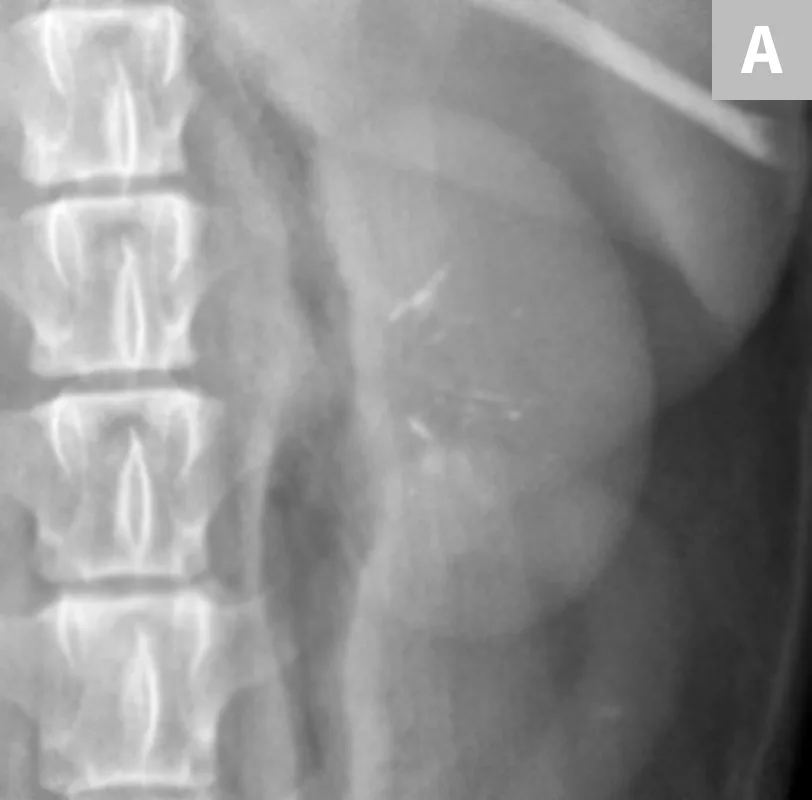

FIGURE 3A

Close-up radiograph of the left kidney with a large, smoothly margined renal calculus in a clinically normal canine patient.